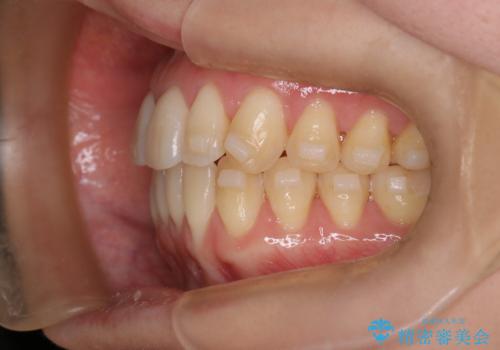

【インビザライン】反対咬合を治したい

- 前歯の反対咬合を主訴に来院されました。

インビザラインにて歯列弓の拡大により叢生の改善を行うことができ、患者様にも満足していただました。

前歯の反対咬合は歯牙への負担も大きくできるだけ早期に治療を行うことを推奨しています。